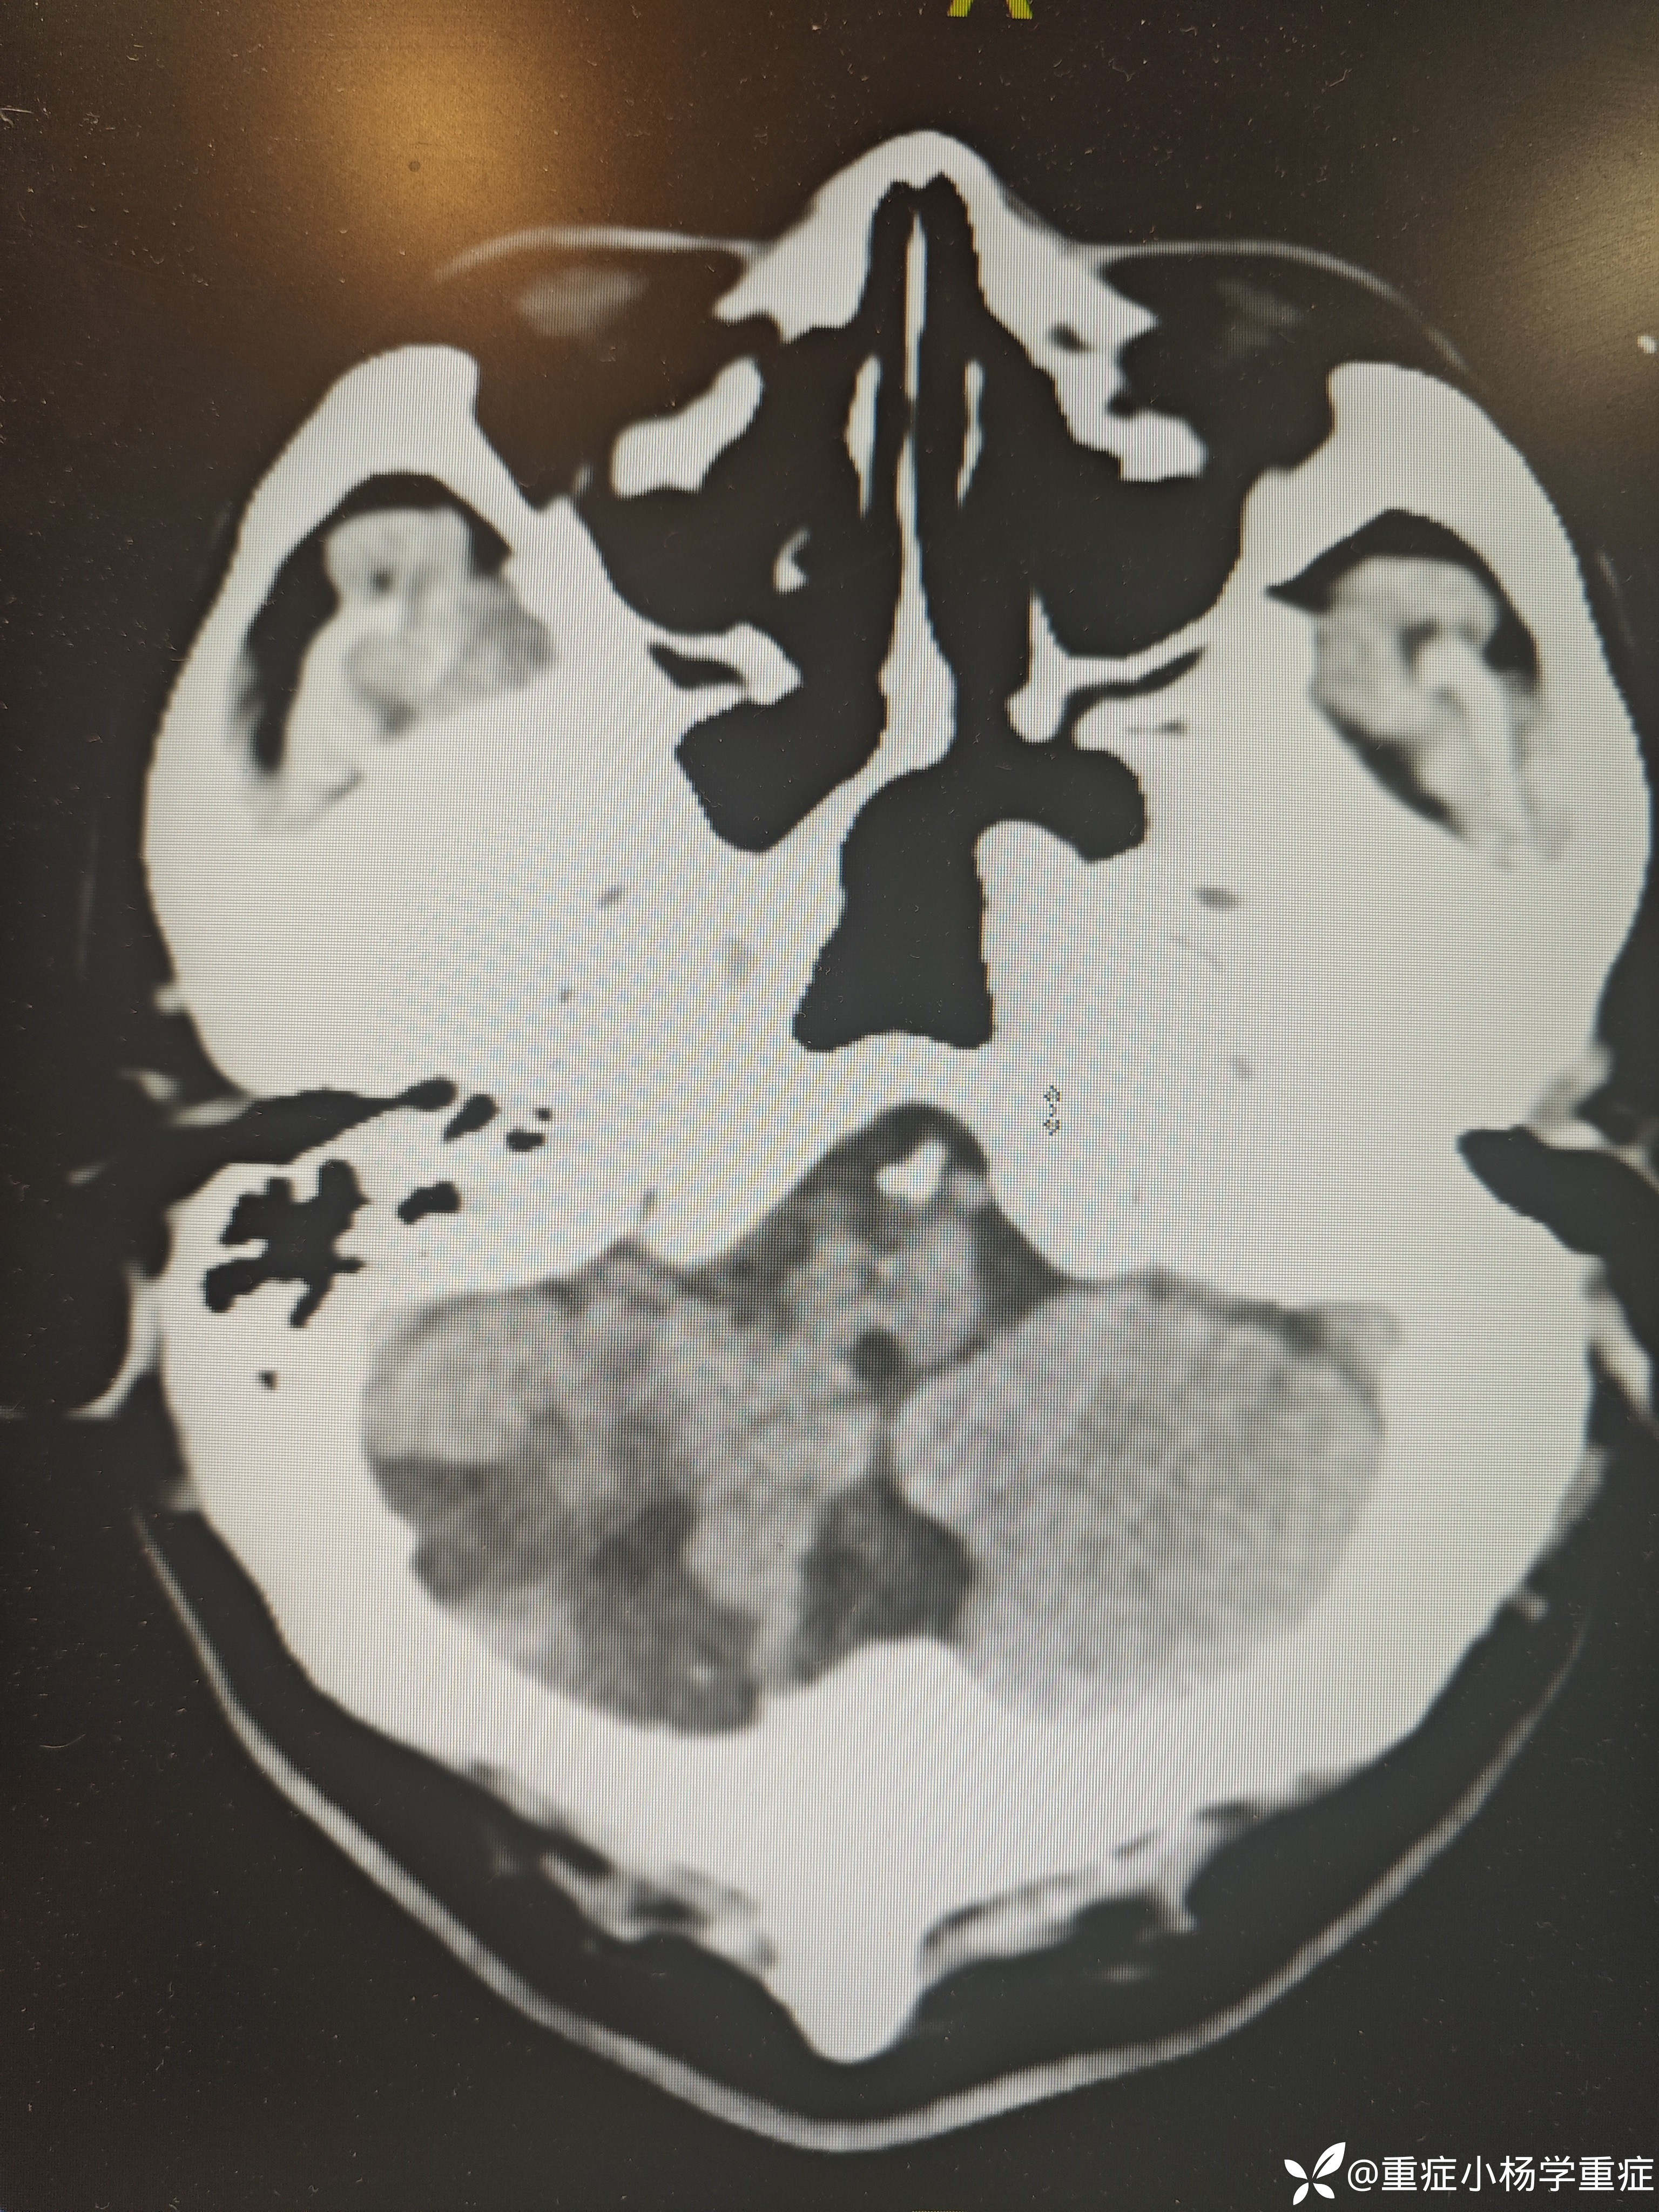

飞跃迷雾1 达人已点赞因“代:脑出血术后2月余,痰多伴呼吸困难1小时”入院。因头痛至医院检查ct提示蛛网膜下腔出血,后完善CTA提示脑血管畸形,至省内医院行介入栓塞后出现脑梗塞,考虑压迫延髓导致呼吸功能损伤,术后第二天予以气切,后出现四肢瘫痪,近期ct如下